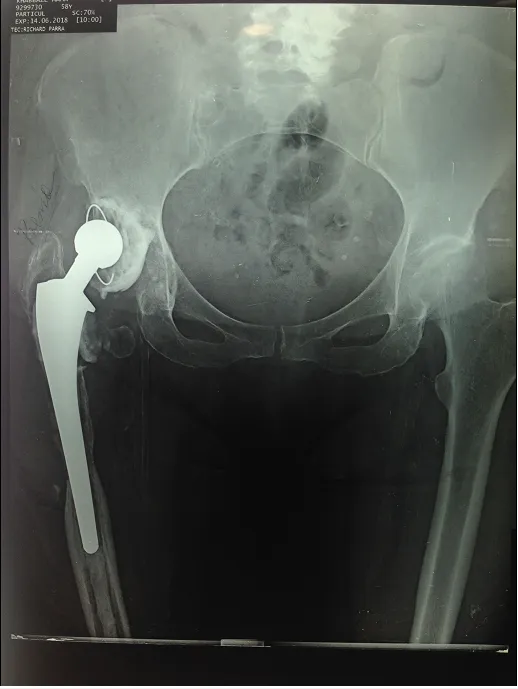

Dislocation of the hip prosthesis

We are talking about a dislocation of the hip prosthesis when the artificial femoral head comes out of the prosthetic acetabulum. Functional disability, pain and shortening of the lower limb are the main manifestations of dislocation of the prosthetic femoral head.

Radiological diagnosis is obvious most of the time and easy to detect.